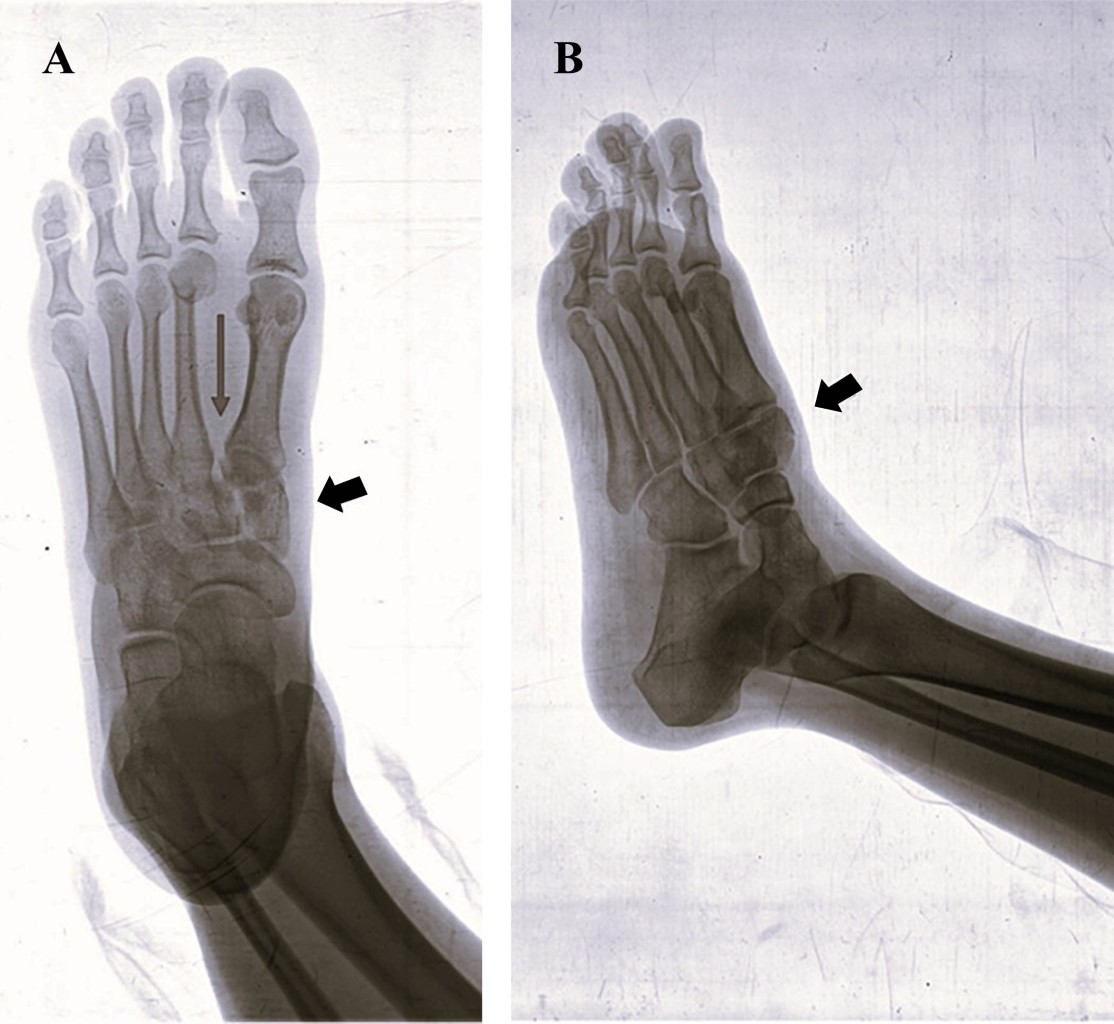

Figure 4